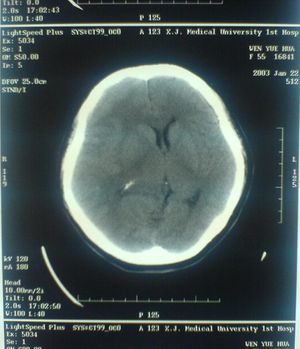

الأشعة المقطعية أو التصوير المَقْطَعي الحاسوبي Computed tomography نظام تصوير بالأشعة السينية، يُسْتخدم لتصوير مختلف أجزاء الجسم مثل الرأس والقلب والبطن. ويستعين الأطباء بالتصوير المقطعي الحاسوبي على تشخيص الأمراض وعلاجها. وتسمى هذه التقنية أيضًا التصوير المقطعي المحوسب أو التصوير المقطعي المحوري المحوسب.

ويستعمل الأطباء فحوص التصوير المقطعي الحاسوبي لتشخيص كثير من الحالات مثل الأورام والإصابات وتجلطات الدم وكسور العظام. ويساعد التصوير المقطعي الحاسوبي أيضًا في معالجة بعض الأمراض، التي قد تتطلب جراحة بطريقة أخرى. فمثلا،ً يمكن للأطباء استعمال التصوير المقطعي الحاسوبي لإرشادهم إلى إدخال القثطار (أنبوب رفيع) إلى خُرّآج في الجسم لسحب الصديد من المنطقة الملوثّة.